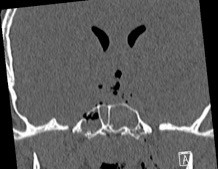

- de brèche ostéo-durale de la base : rhinorrhée, risque de méningite (cf. ci-dessous)

y a-til un risque de méningite ?

- si rhinorrhée cérébro-spinale

- si plaie pénétrante : parfois méconnue car cachée dans le cuir chevelu, les cavités nasales